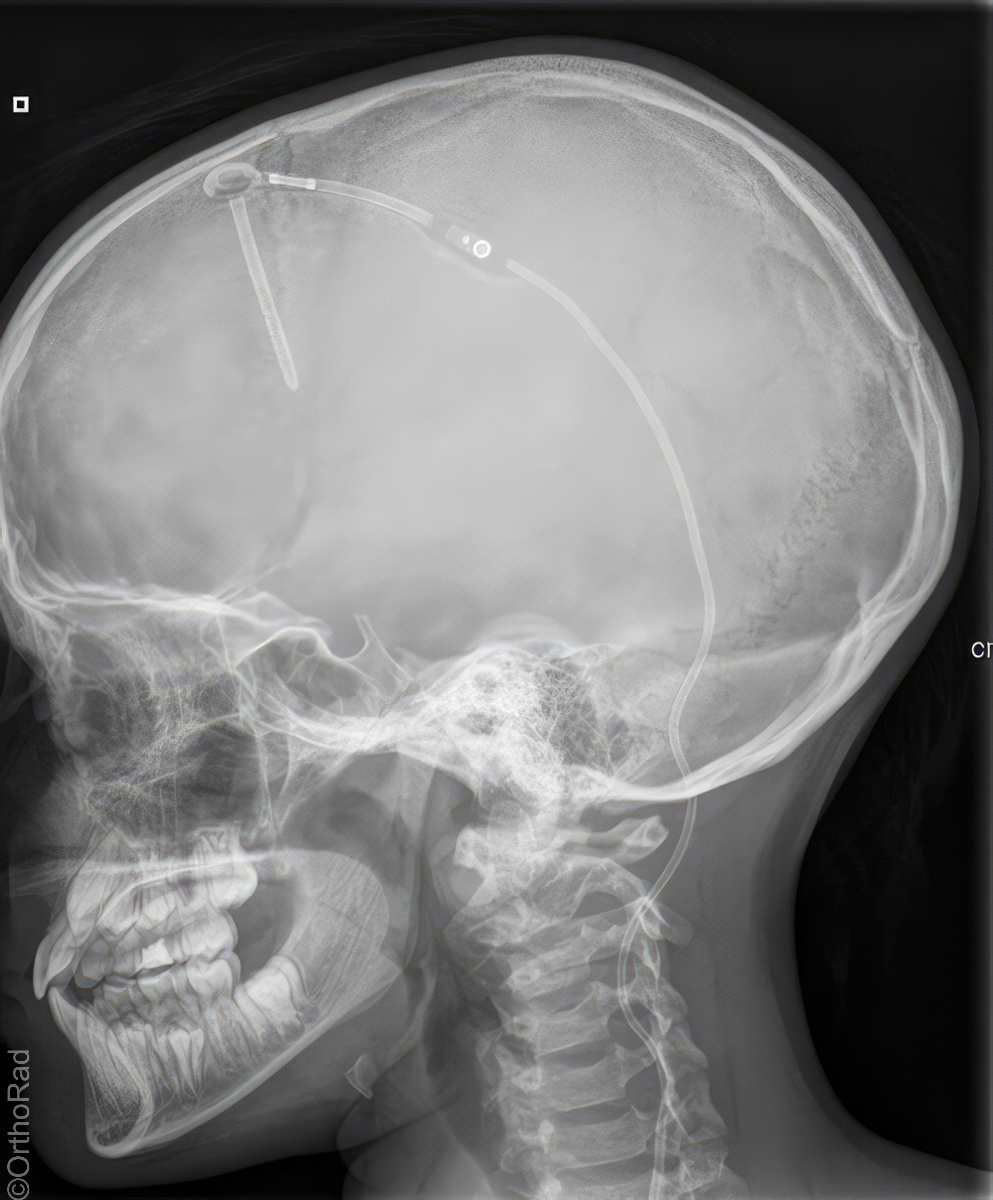

Schädel lateral

Indikation

Fremdkörper-Lokalisation vor MRT, Shuntventil-Kontrolle

Lagerung

Schräg-Bauchlage mit aufstützender Hand der anliegenden Schädelseite

Beine leicht angezogen

Kopf streng seitlich

Medianebene parallel zum Tisch

Kinn und Stirn auf einer gedachten Linie (D.-H. nicht relevant)

Qualitätskriterien

Vollständige Darstellung des gesamten Schädels, weitgehend deckend der Konturen, vordere und hintere Schädelgrube, Orbita, Kieferhöhlen und Jochbein. Zudem deckungsgleich von kleiner Keilbeinflügel und äußerer Gehörgang. Strichförmige Abbildung der Sella turcica.